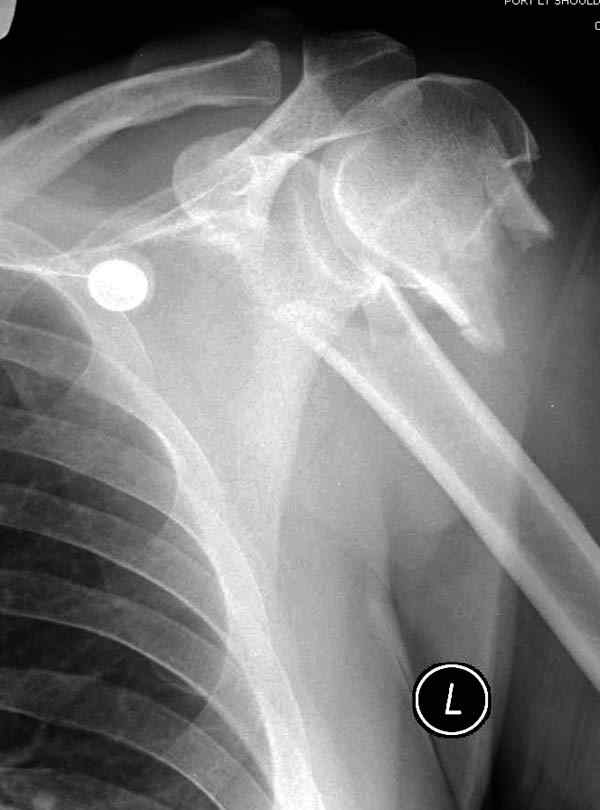

Пациентка Б.1953 г.р., врач-терапевт. Травма 27.11.08г. Падение с высоты роста. Выявлен закрытый не осложненный оскольчатый перелом хирургической шейки левого плеча со смещением. 02.12.08г. оперирована. Выполнена открытая репозиция и остеосинтез пластиной LCP Деост с дополнительной фиксацией отдельно лежащего фрагмента винтом. Послеоперационный период протекал без особенностей, заживление раны первичным натяжением. Швы сняты через 10 дней. Иммобилизация левой верхней конечности клиновидной подушкой 4 недели. По окончании срока – рентген-контроль и умеренная разработка плечевого сустава. В течении месяца функция левого плечевого сустава восстановилась удовлетворительно: поднятие руки до 110 гр., отведение - 90 гр. и до 110 гр. отведение с лопаткой. Отведение руки назад – 20 гр. Наружная и внутренняя ротация – 20 гр. Пациентка по настоянию самостоятельно вышла на работу. 27.03.09 при контрольном осмотре жалоб не предъявляет, болевой синдром в левом плечевом суставе отсутствует. Отведение плеча активно до 90 гр, пассивно с лопаткой до 110 гр., поднятие – 110 гр, отведение назад 20 гр, наружная и внутренняя ротация по 20 гр. На контрольных рентгенограммах отмечается смещение металлоконструкции, ротация головки плеча с приведением дистального отломка на 13 гр. и смещением к зади на 30 гр. Рентгенограммы прилагаются. Ваш взгляд на дальнейшую тактику лечения пациентки?

Нет аксиальной проекции сразу после вмешательства. Возможно, никакого значительного смещения нет, все осталось так, как первично сопоставили...и,

Уважаемый Евгений, похоже, что первый и второй Р-снимки выполнены несколько в разных положениях(ротация) плечевой кости, в связи с этим создается впечатление смещения пластины. Остеосинтез выполнен при угловом смещении отломков.Таковым и остался. Данная ситуация была бы очевидна гораздо раньше, если бы при контрольной Р-графии были выполнены снимки в 2-х проекциях.(Не в обиду, сам иногда выполняю только один).